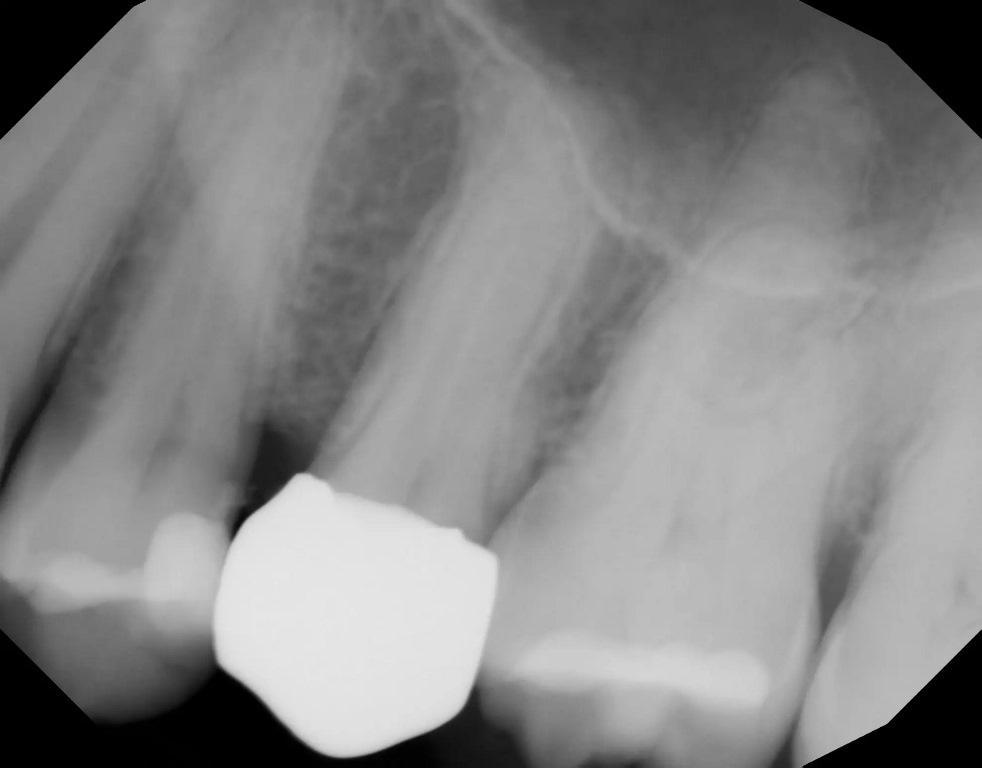

На повторном плановом профилактическом приеме через пять лет была сделана периапикальная рентгенограмма (фото 12). Как было отмечено на предыдущих контрольных рентгенограммах, периапикальная рентгенопрозрачность отсутствовала, что свидетельствует об успешном лазерном лечении в предотвращении периапикальной патологии и инфекции пульпы.

Фото 12: Периапикальная рентгенограмма, сделанная через пять лет после лазерного удаления пульпы и реставрации зуба, не выявила периапикальной патологии.